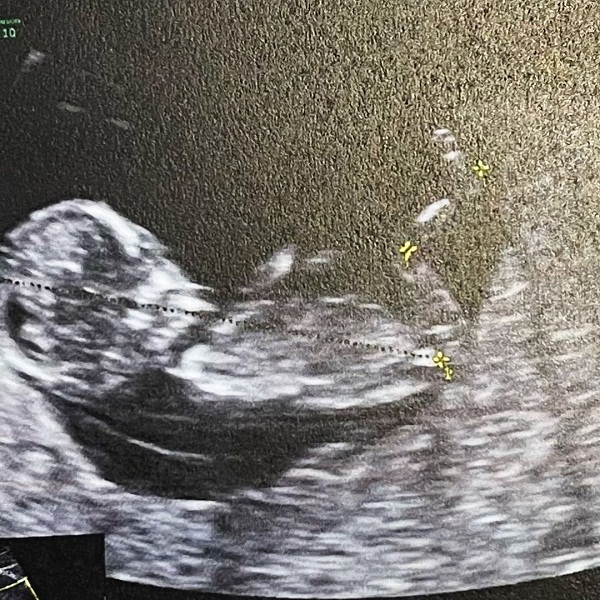

ทำเอาลุ้นกันหนักมาก สำหรับลูกคนแรก ของสาว น้ำชา ชีรณัฐ ที่ล่าสุดเจ้าตัวก็ได้ทำคลิปเฉลยเพศแล้ว ชื่อว่า ลุ้นหนักมากเฉลยเพศลูก BOY or GIRL? โดยในคลิป ได้เฉลยเพศลูกว่าเป็นลูกชาย ซึ่งสามีของน้ำชาก็เล่าความรู้สึกแรกว่า นี่คือ ดีใจมาก ได้คนแรกก็ลูกชายแล้ว ไม่เคยเป็นพ่อใคร แล้วเราจะเลี้ยงได้ดีไหม แต่ว่าแน่นอนดีใจ เป็นครั้งแรกเนาะ แต่ก็ต้องพยายามทำให้ดีที่สุด ด้านสาวน้ำชา เผยว่า ก็รู้สึกว่าดีค่ะ เพื่อนๆ ที่เขาได้ลูกชาย เขาก็บอกว่าจริงๆ แล้วลูกชายน่ารักมาก รักเขาแบบนี้ เขาเป็นเขาไม่ว่าจะยังไงก็ตาม เราก็ทำหน้าที่ของเราให้ดีที่สุด จะผู้หญิงจะผู้ชายอะไรก็คือ เต็มที่ รักหมด แต่เผอิญได้ผู้ชายคนแรก ต้องหล่อแน่ๆ เลย ต้องจมูกโด่ง เราทั้งคู่จมูกโด่ง

ขอขอบคุณภาพ IG namcha_tea / dilakalathapipat